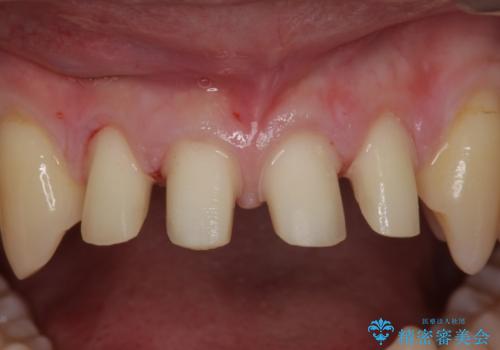

- 前歯のすき間を気にして来院。

矯正治療か、セラミックで最短で治すかの選択肢を提示し、セラミックで治すことにしました。

全て神経は取らずに、削りました。